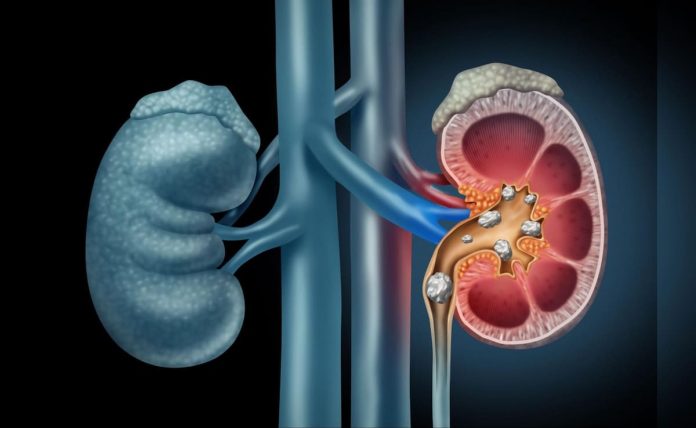

उत्तर प्रदेशातील बागपत येथून एक धक्कादायक प्रकरण उघडकीस आले आहे. वास्तविक, एखाद्या व्यक्तीने आपल्या शरीराचे वजन कमी करण्यासाठी ऑनलाइन औषधे ऑर्डर केली होती. हे औषध खाल्ल्यानंतर, त्या व्यक्तीची मूत्रपिंड खराब झाली आणि त्याचा मृत्यू झाला. हे प्रकरण उघडकीस येताच त्या भागात एक ढवळून घसरला.

मताला 40 वर्षांच्या फुरकान म्हणून ओळखले गेले आहे. कोणतीही सुधारणा नाही आणि डायलिसिसनंतरही त्याचा मृत्यू झाला.

त्याच वेळी, आरोग्य विभागाच्या अधिका official ्याने डॉक्टरांच्या सल्ल्याशिवाय कोणतेही औषध न घेण्याचे आवाहन केले आहे. वास्तविक, आपण सांगूया की हे प्रकरण बागपाट शहरातील कोटवाली भागात आहे जेथे मटा कॉलनीत राहणा SP ्या एसपी नेते फुरकान पहलवानने फेसबुक आणि यूट्यूबवर जाहिराती पाहिल्यानंतर औषधे मागितली होती, ज्यात माल मिसळल्या गेल्या अजमोदा (ओवा), सोनफ आणि जिरे आणि त्या युवकाने एका महिन्यासाठी एक उपाय केला.

मृत फुरकानचा भाऊ इरफान म्हणाला की फुरकानचे वजन वाढत आहे. हे कमी करण्यासाठी त्याने सोशल मीडियावरून औषधे मागितली आणि ते देखील खाल्ले. काही दिवसांत त्याचा प्रभाव देखील दिसला, परंतु भावाची अचानक तब्येत बिघडली. आणि नंतर मरण पावला.

दिल्लीत डॉक्टरांनी सांगितले होते की त्यांनी काही चुकीचे औषध घेतले आहे, ज्यामुळे त्यांचे मूत्रपिंड खराब झाले आणि डायलिसिस घेण्याचा सल्ला दिला, परंतु ते पूर्ण झाले नाहीत आणि जर ते तांत्रिक डॉजमध्ये पडले तर त्याने लाखो रुपये घेतले आणि रविवारी खराब झालेल्या स्थितीमुळे ही स्थिती खराब झाली. त्याच वेळी, बागपत मधील डॉक्टर म्हणतात की डॉक्टरांच्या सल्ल्याशिवाय, कोणतेही औषध ऑनलाइन मिळत नाही आणि त्याचा सेवन करू नका, यामुळे जीवन देखील होऊ शकते.